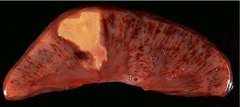

Necrotic Lesion

Front

Back